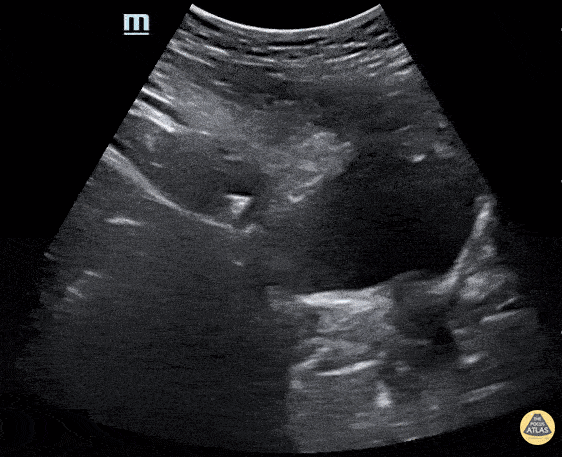

Renal/GU - UVJ stone with ureteral dilation

A young female presented with acute RLQ abdominal pain and found to have a 5mm right ureter stone at the UVJ with ureteral dilation. The patient also had moderate hydronephrosis. Matthew Petruso, DO; Harpreet Grewal, MD; Eric Versluis, MS4; Central Michigan University: Emergency Medicine Residency.